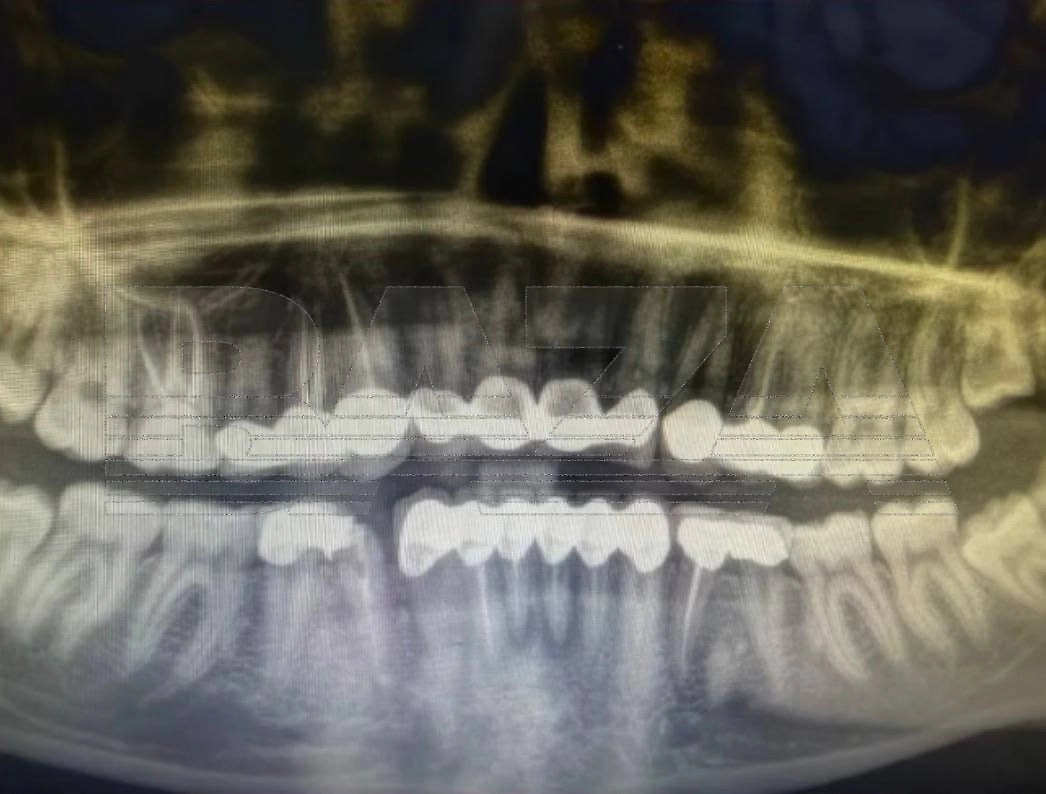

По словам девушки, в марте она обратилась в турецкую клинику для установки виниров. Во время процедуры зубы спилили настолько сильно, что от нижних почти ничего не осталось. Позже пациентка выяснила, что вместо виниров ей фактически установили коронки и мосты на несколько зубов. Уже на следующий день после процедуры появилась сильная боль.

В клинике начали удалять воспалённые нервы — их оказалось целых шесть. Через некоторое время боль вернулась. Таблетки не помогали, поэтому она обратилась в экстренную стоматологию, где врачи обнаружили сильное воспаление и срочно удалили ещё несколько нервов. На следующий день у пациентки сильно опухла щека. Медики предупредили, что инфекция начала распространяться и при более позднем обращении могла потребоваться госпитализация. Кроме того, одна из установленных коронок треснула.

Сейчас ей предлагают новое лечение. Одну конструкцию заменить отдельно нельзя — придётся ломать соседнюю и делать двойную. Стоимость восстановления оценивается примерно в две тысячи долларов, а пока девушке приходится ждать, пока спадёт воспаление.